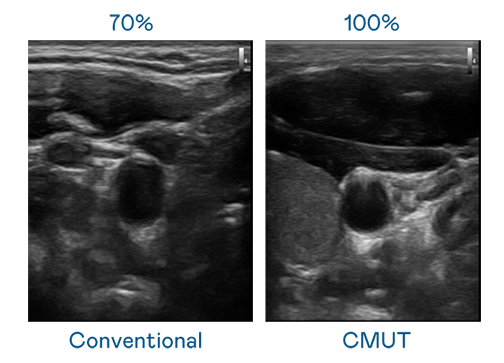

CMUT 技术是一种用电容式微机电元件来产生超音波讯号的技术。与传统 PZT 压电式技术相比,CMUT 频宽增加 30%,更宽频的超音波讯号让影像解析度大幅提升,是实现高影像品质医疗超音波扫描、促进精准医疗发展的关键技术。

超音波影像的解析度高低,首先取决于探头能发出的讯号频宽。BG大游 CMUT 可提供高清晰的超音波讯号,提供高频宽、高灵敏度、影像纹理细节更高的超音波影像,协助医护人员缩短影像判读时间及利用精准的医疗影像进行诊断。